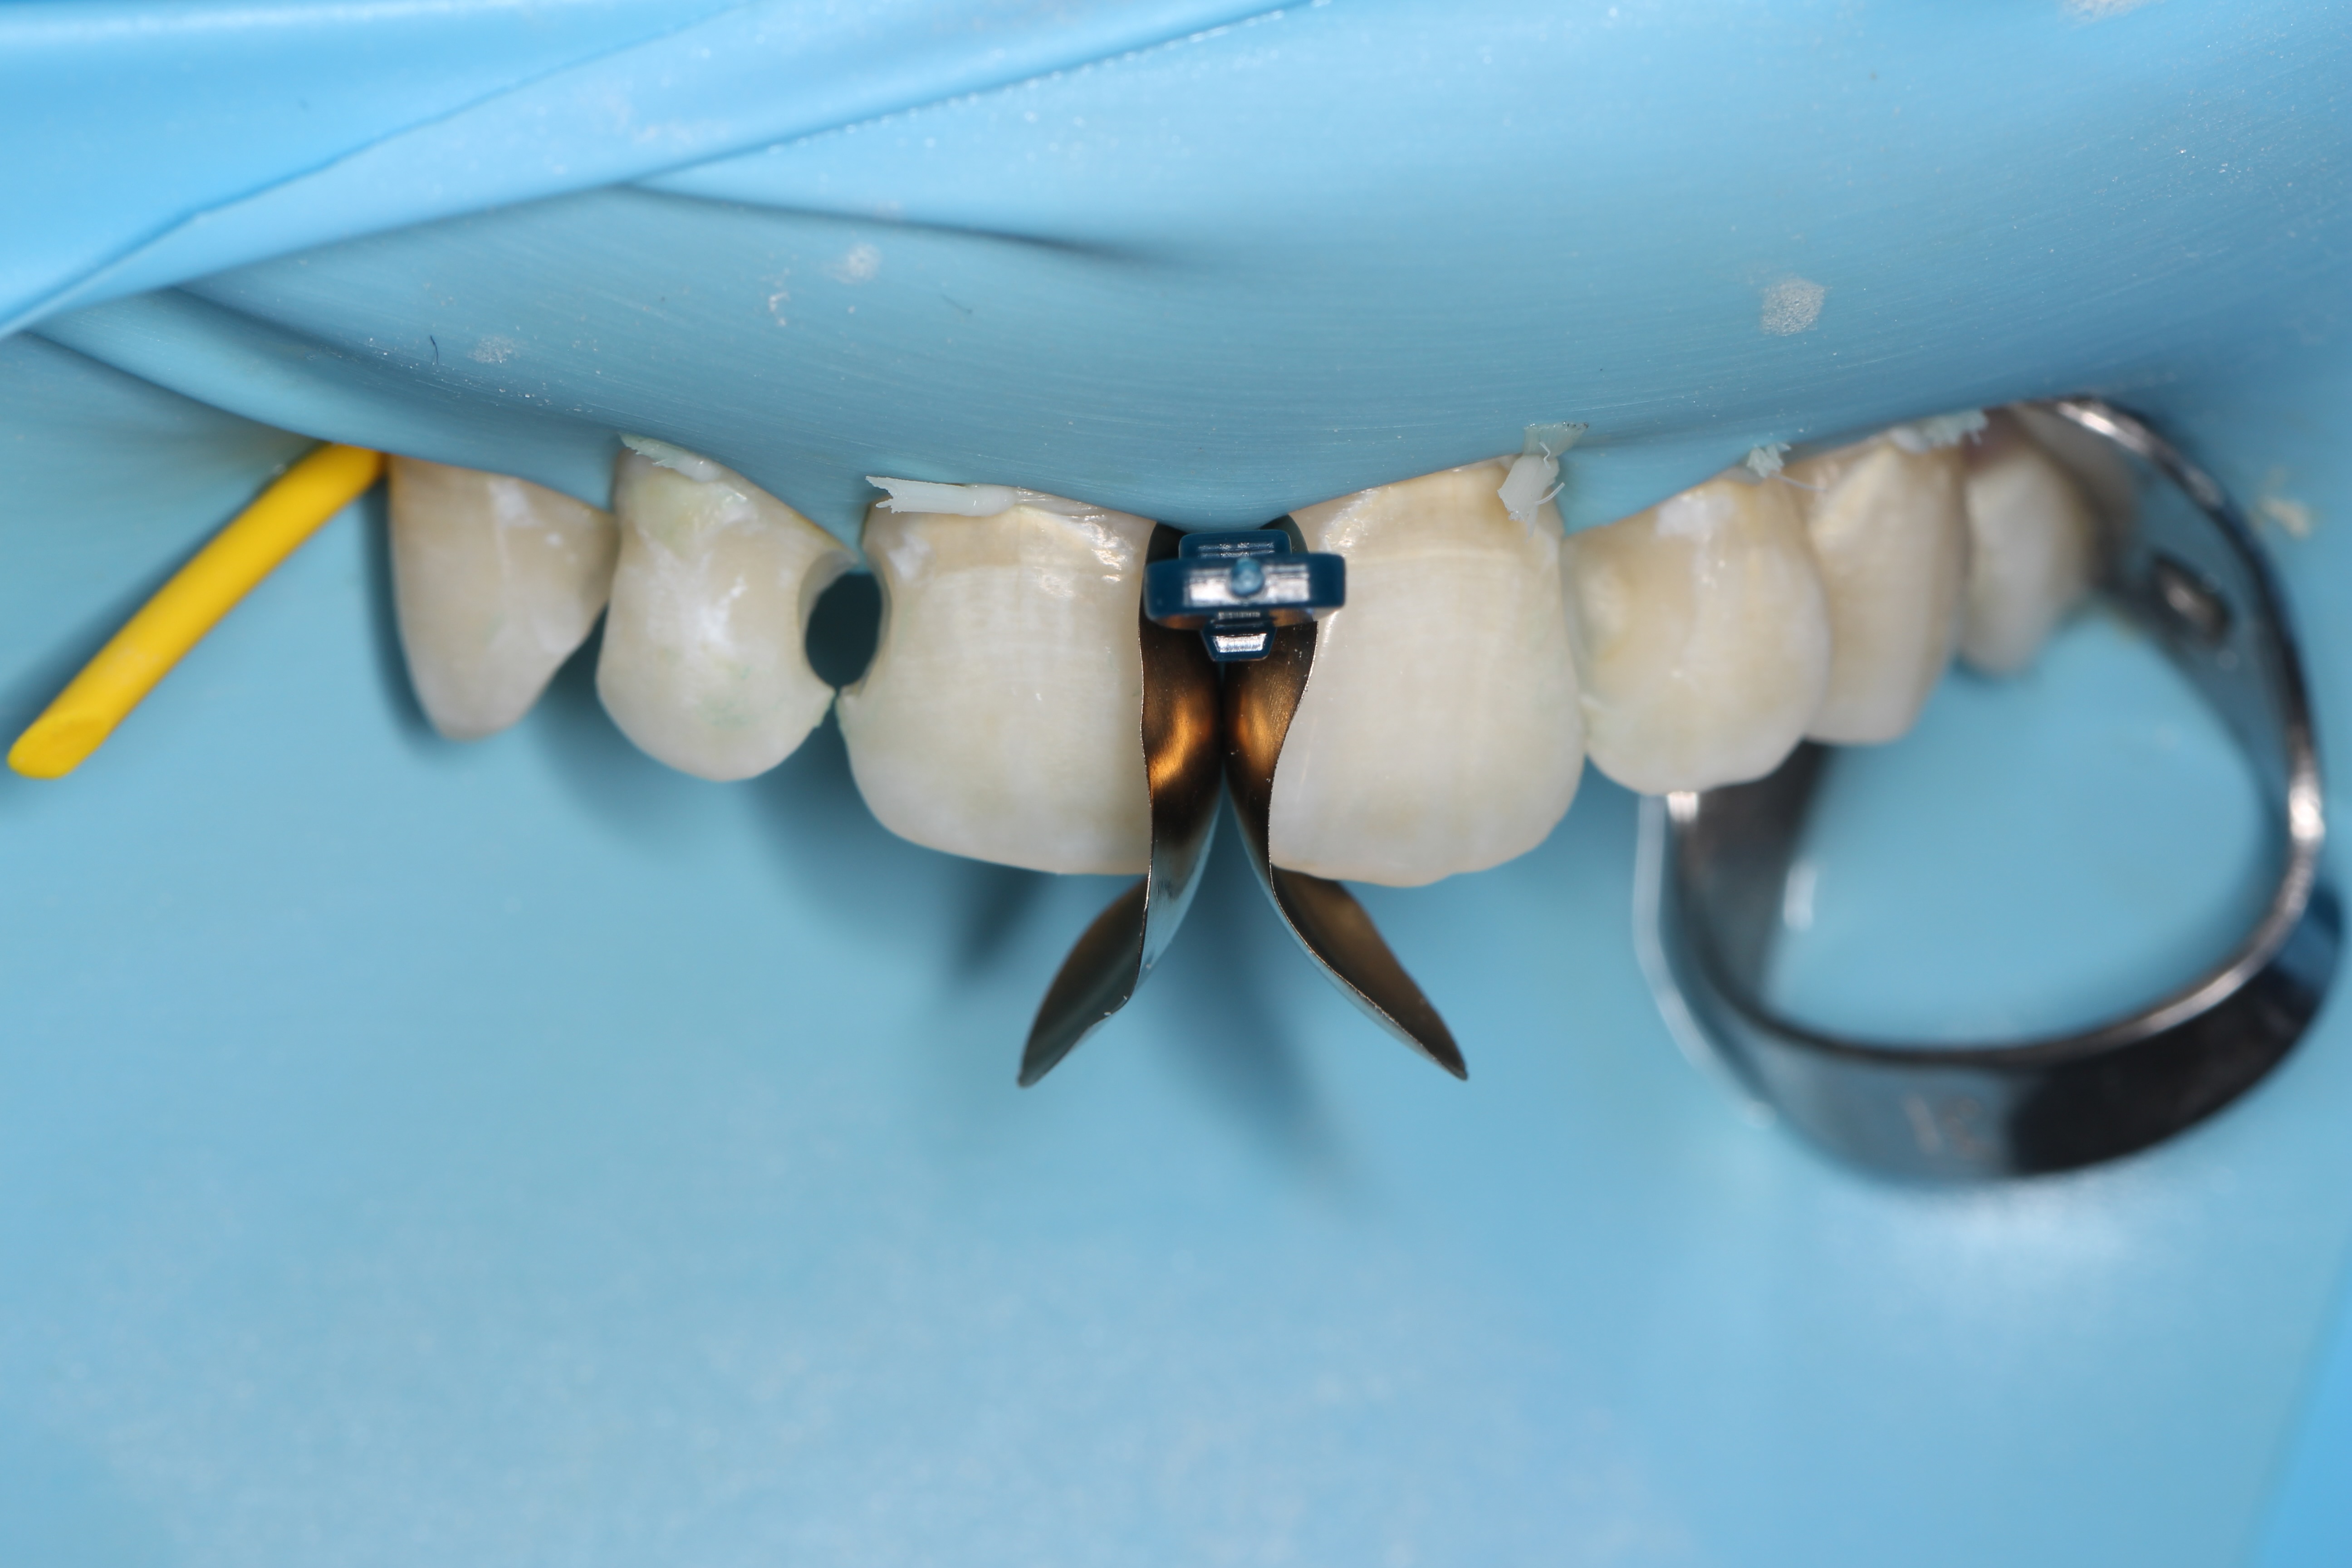

Crowns and onlays by Professor Brian Millar

This course solidified my knowledge and allowed me to practice various cuspal coverage treatments including overlays, onlays and vonlays. I was able to learn about the different preparation techniques and margins required for each indirect material.